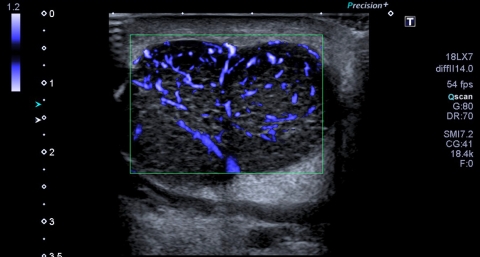

Fig. 1. Echographie avec doppler SMI d’un lymphome folliculaire parotidien.